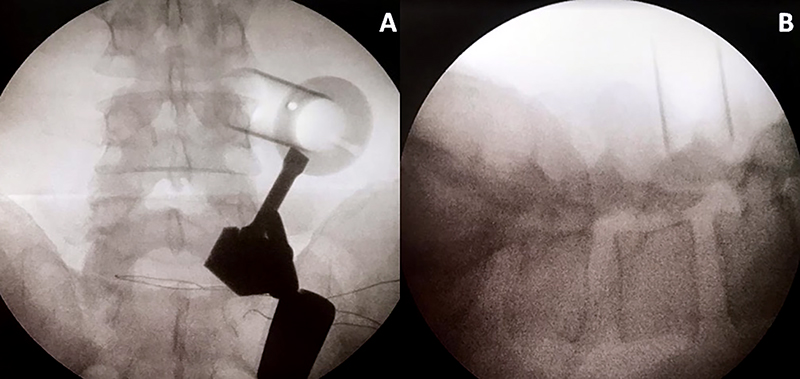

El tubo debe dirigirse al espacio intertransverso del disco a tratar, teniendo como límites del espacio de trabajo, las apófisis transversas a nivel superior e inferior y las apófisis articulares medialmente. Esto se corrobora realizando radioscopia con incidencia anteroposterior y perfil (fig. 1).

Figura 1: Radioscopía intraoperatoria. Colocación del sistema tubular mínimamente invasivo.